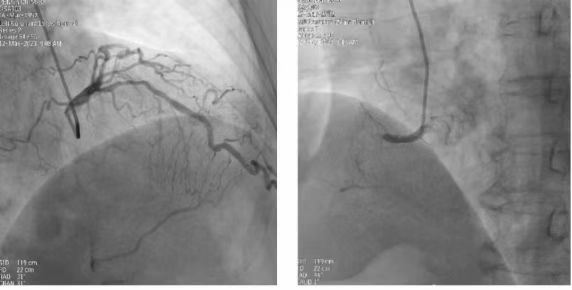

Pusat kardiovaskular dan serebrovaskular Rumah Sakit Changsha Jingkai dibangun bersama oleh klinik rawat jalan kardiovaskular dan bedah, bangsal umum, CCU, dan pusat intervensi. Diagnosis dan pengobatan...